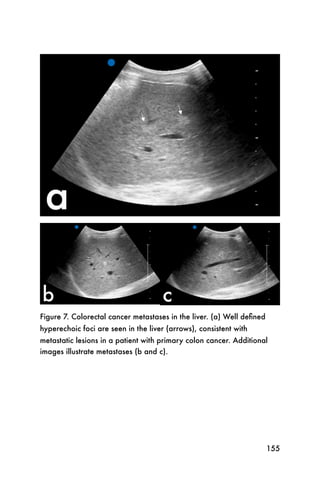

can be useful in determining the probability of

cholecystitis and progression to further disease. After

visualizing the gallbladder in a longitudinal view, the